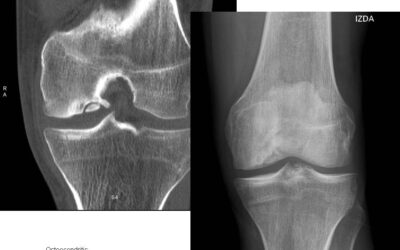

¿Qué es la Osteocondritis?

¿Qué es la Osteocondritis? La Osteocondritis es una afección muy preocupante pues se asemeja en gran medida a los síntomas de un infarto. Pues se trata de la inflamación de los cartílagos que unen a las costillas con el esternón. Representa un problema bastante...